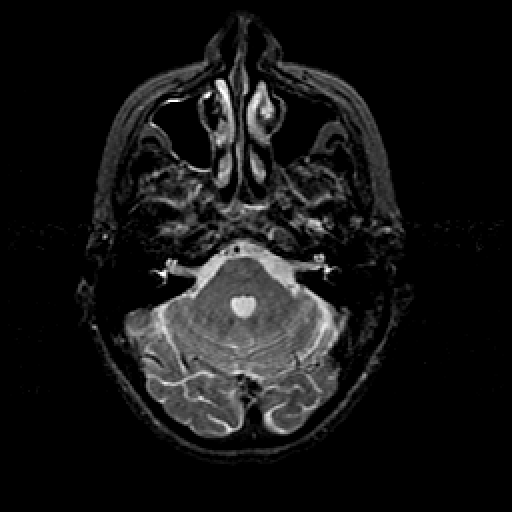

T2-weighted structural MR: Slice 14

Slice 14